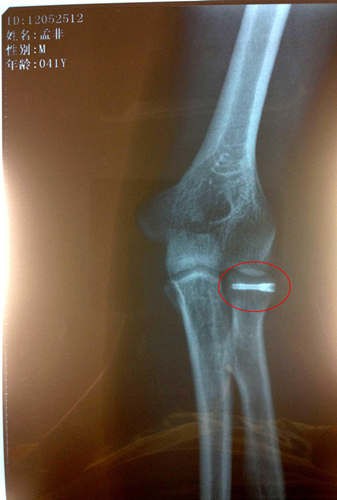

孟非打鋼釘x光片

自孟非不慎跌落舞臺之后,他的傷情也是牽動了無數(shù)人的心。據(jù)悉,在孟非回到南京后立即接受了手術且手術進行地非常成功,術后一直在家中休養(yǎng)。最近傷勢恢復地很好,已經(jīng)不再用石膏和繃帶固定了,而是改成了鈦合金鋼釘固定,上周日“孟非粉絲團”的微博也首度曝光了孟非打著鋼釘?shù)腦光片。根據(jù)目前的情況,醫(yī)生預計傷愈時間會大大縮短。根據(jù)最近錄制計劃,本周末《非誠勿擾》恢復錄制,打著鋼釘?shù)拿戏且灿诮袢罩鼗毓ぷ鲘徫?,而對于孟非本周打著鋼釘回歸錄制,很多人則大贊勞模孟非是“主持人界的鋼鐵俠”

據(jù)了解,確診撓骨骨折的孟非在家中休養(yǎng)已經(jīng)有半個月時間,專心養(yǎng)傷術后恢復情況很好,孟非在家每天要保證一定時間的康復訓練,在家全身心的養(yǎng)傷給了他最大程度的休息,接受手術的左手手臂已不用打著厚厚的石膏,不用吊著繃帶固定,孟非還開玩笑:“現(xiàn)在的醫(yī)療技術很先進,傷口處打上了一根鈦合金的鋼釘,就這樣一處理,然后就不用繃帶石膏里一層外一層的包了?!笔軅诩业拿戏且搽y得偷閑,陪陪家人,看看書,溜溜狗。